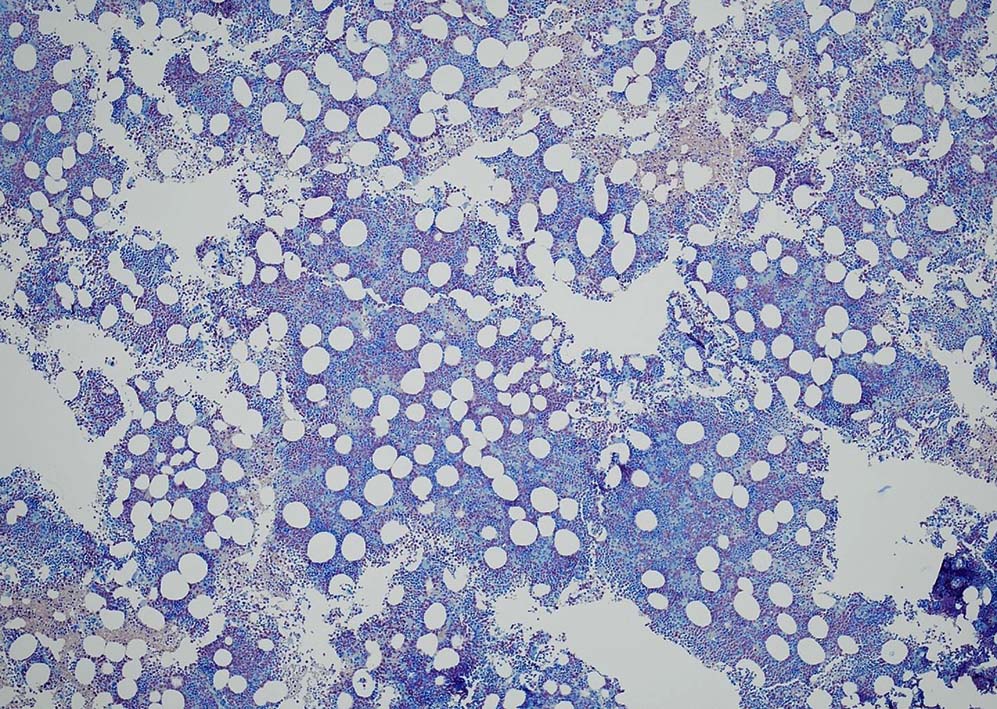

Megakaryopoiesis; Mgkは増加している. 多数の分離円形核巨核球が出現している. microMgkが増加している.